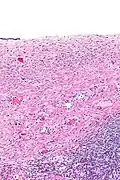

| Ovarian serous cystadenoma. The cystic space is at the top of the image. Ovarian parenchyma is seen at the bottom right. H&E stain. | |

Serous cystadenomas are diagnosed by histomorphologic examination, by pathologists. Grossly, they are, usually, small unilocular cysts that contain clear, straw-coloured fluid. However, they may sometimes be multilocular. Microscopically, the cyst lining consists of a simple epithelium, whose cells may be either:[4]

- be columnar and tall and contain cilia, resembling normal tubal epithelium

- be cuboidal and have no cilia, resembling ovarian surface epithelium